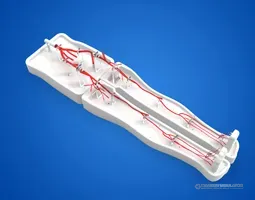

Radial Artery Puncture Operation Model (Ultrasound Guided) adalah simulator lengan bawah untuk pelatihan kanulasi arteri radialis dengan panduan USG. Arteri radialis dibuat berdasarkan data CT manusia.

Material komposit khusus memungkinkan visualisasi arteri yang jelas di layar USG *real-time*. Memberikan sensasi ‘tembus’ (*breakthrough*) yang realistis saat jarum menembus dinding arteri.

Drawing of Radial Artery Puncture Operation Model (Ultrasound-Guided)